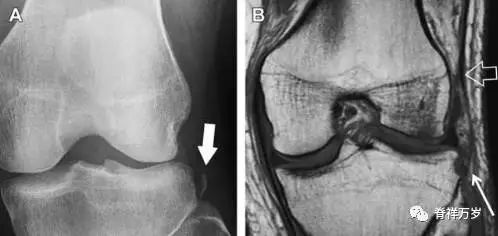

膝关节撕脱骨折和压缩骨折常伴发于韧带损伤,若想准确诊断,在了解这些骨折高发部位的同时,还需仔细认真地阅片,否则有些骨折就被漏诊了。

8前交叉韧带胫骨髁间嵴撕脱骨折

前交叉韧带撕脱骨折常发生在胫骨髁间嵴(图 1)。这种骨折在青少年中常见,但在成年人中也并不像大家想象的那么少见。

图 1 摩托车事故患者前交叉韧带撕脱性骨折

A 正位片示胫骨髁间嵴底部骨折(箭头),注意别把这个骨折碎片错认为关节内结构。B 侧位片示胫骨上方可见一细长型骨折碎片(椭圆)。C MRI 矢状位 T2 加权像示前交叉韧带附着于撕脱的骨折碎片上(箭头),注意周围存在骨髓水肿和积脂血征(空箭头)。

9股骨外侧髁凹陷征

图 2 扭伤后的股骨外侧髁凹陷征

A 侧位片示股骨外侧髁凹陷。B MRI 矢状位 T2 加权像示股骨外侧髁及胫骨后外侧骨挫伤(空箭头)。胫骨近端随着后交叉韧带撕裂发生移位,露出外侧半月板的后角(弧形箭头)。